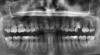

RrranDom Опубликовано 23 ноября, 2010 Поделиться Опубликовано 23 ноября, 2010 Уважаемые специалисты, посмотрите, пожалуйста, снимок. Зуб – 6ка верхняя левая (т.е. справа на снимке)Раньше там стояла пломба (несколько раз переставляли в течении n лет, стесывая в процессе зуб) и на нее сверху советовали поставить коронку. Но время было упущено, пломба выпала и теперь просто поставить коронку, говорят (врачи), нельзя. Надо удалять весь зуб и дальше выбирать, что ставить вместо. Мне же часто встречалось мнение, что свой зуб надо стараться сохранить как можно дольше и не спешить его вырывать.Гляньте, пожалуйста, может все-таки есть шанс зацепиться за остатки зуба и поставить коронку на него? Спасибо. Ссылка на комментарий

L . O . M . Опубликовано 25 ноября, 2010 Поделиться Опубликовано 25 ноября, 2010 (изменено) Теоретически протокол восстановления зубов со степенью разрушения как у Вас существует , но ... Разрушение зуба не должно быть ниже уровня костной ткани . Гарантировать , что у Вас не так только по снимку невозможно , надо снять остатки пломбы , кариеса и , если оставшийся объём тканей позволяет , провести восстановление с помощью вкладки и коронки . Ну и , конечно же , перед восстановлением нужно будет перелечить корневые каналы . Изменено 25 ноября, 2010 пользователем L . O . M . Ссылка на комментарий

alexanch Опубликовано 7 декабря, 2010 Поделиться Опубликовано 7 декабря, 2010 Теоретически протокол восстановления зубов со степенью разрушения как у Вас существует , но ... Разрушение зуба не должно быть ниже уровня костной ткани . Гарантировать , что у Вас не так только по снимку невозможно , надо снять остатки пломбы , кариеса и , если оставшийся объём тканей позволяет , провести восстановление с помощью вкладки и коронки . Ну и , конечно же , перед восстановлением нужно будет перелечить корневые каналы .восстановить разборной культевой вкладкой,но перед восстановлением сделать прицельный снимок зуба на качество пломбирования каналов Ссылка на комментарий